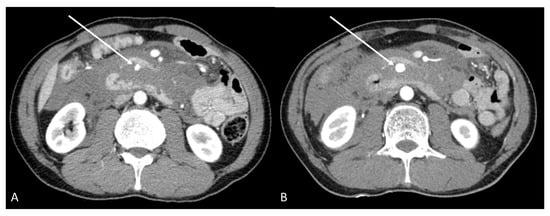

2. Case Report